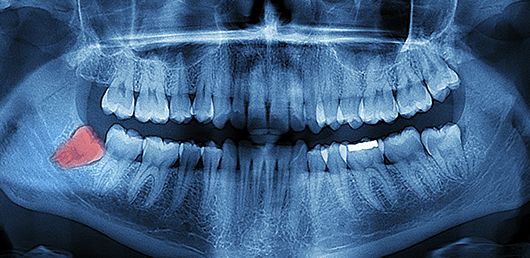

Hablemos sobre las muelas del juicio, desvelaremos por qué son denominadas de esta manera y cuál es su función en nuestro organismo. A lo largo de nuestra vida, es probable que hayamos escuchado sobre las muelas del juicio y sus implicancias en nuestra salud bucal. Sin embargo, pocos conocen el origen de su nombre y la importancia que estas piezas dentales tienen en nuestra boca.